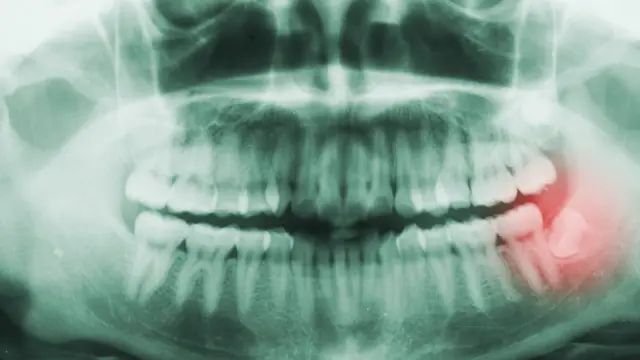

Он вспоминал, как в 1960-е годы полярники рассказывали о том, что у них внезапно раскалывались зубы, однако в тот момент это считалось результатом воздействия экстремальных морозов.

Он, впрочем, считает, что реальной причиной проблемы был кариес (гниение зубов), вызванный диетой с высоким содержанием сахара.